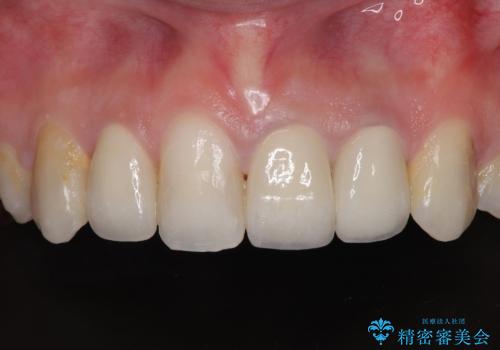

- 前歯のデコボコと、その結果むし歯が進行していることを気にして来院された患者様です。

前歯や奥歯の根管治療を行い、その後上下左右の第一小臼歯4本を抜歯してワイヤー装置にて矯正治療を行うこととしました。

矯正治療後には、根管治療を行った歯をオールセラミッククラウンにて補綴治療を行うこととしました。